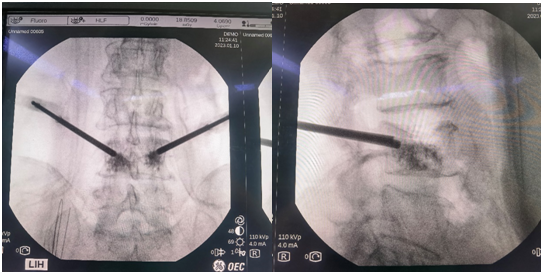

经MRI及CT检查示:腰4椎体压缩性骨折。经专家讨论后,医疗团队拟采用机器人辅助,局麻下行经皮球囊扩张椎体成形术。经过精密的仪器调试和配准,术前进行了反复的模型演练。刘时璋主任团队将患者的CT数据与机器人系统配准,工程师团队将事先规划好的个体化穿刺路径数据植入机器人系统。将术中的正侧位X线透视数据与CT数据融合后,机械臂按照术前规划路径,一次性穿刺成功,位置精准满意。

传统手术徒手穿刺需要在反复透视下,多次调整穿刺位置、方向及深度,增加了患者的不适感,且不一定能够达到理想的穿刺位置。而此例患者在脊柱机器人的辅助下,穿刺针精准地置入骨折塌陷位置,促使球囊扩张复位准确高效。穿刺过程中灵敏的压力反馈系统及可调的穿刺速度,大大增加了穿刺过程的安全性,使传统PKP手术更加精准、安全及高效,大大减少了术中透视次数及患者的不适感,同时为一些复杂骨折(如严重骨质疏松,骨性标识不明确;脊柱侧弯、旋转等)的个性化手术方案的实施提供了可能。前期,骨科病院也成功举办脊柱手术机器人培训会,团队认真学习并进一步认识到了骨科手术机器人良好的临床应用潜力,为此次手术的成功奠定了良好基础。